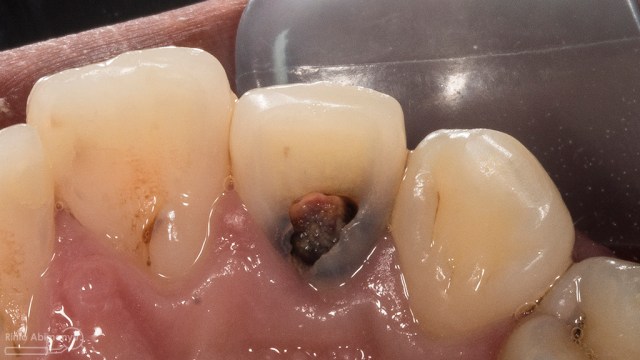

Kasus hari ini tentang gigi-gigi anterior yang fraktur karena kecelakaan lalu lintas. Pasien datang menceritakan kejadian yang dialaminya dan meminta saran bagaimana sebaiknya tindakan yang dilakukan pada giginya…

Begini kondisi klinis saat datang…

Foto klinis gigi-gigi anterior yang mengalami fraktur

Dari pemeriksaan radiografis lokasi fraktur menyerempet kamar pulpa pada ketiga gigi tersebut… Saya sampaikan kepada pasien bahwa ketiga gigi tersebut memerlukan perawatan saluran akar terlebih dahulu baru kemudian dilanjutkan dengan restorasi indirek… kenapa saya pilih restorasi indirek? Pertimbangannya adalah sisa struktur mahkota gigi yang ada bila hanya di “sambung” dengan restorasi direk dalam jangka panjang rentan mengalami kerusakan, yang kedua pemilihan warna akan lebih maksimal pada kasus ini…. Pasien setuju dengan rencan perawatan yang saya jelaskan…